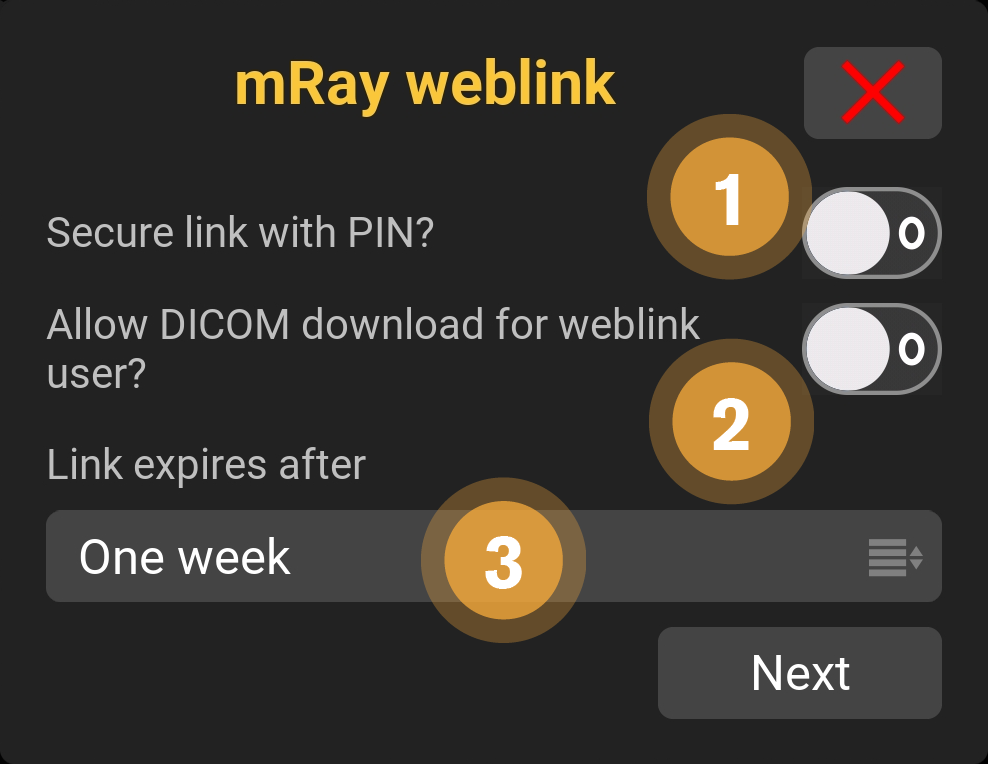

9.14. Link Einstellungen

Wenn Inhalte mit Links geteilt werden, stehen verschiedene Einstellungen zur Verfügung. Die Einstellungen und ihre Funktionen werden im Folgenden erklärt.

-

Hier können Sie entscheiden, ob der Empfänger den Inhalt herunterladen darf.

-

Erlauben Sie hier dem Empfänger, die DICOM Datei zu donwloaden.

-

Wählen Sie die Gültigkeitsdauer für den Link. Die Inhalte sind bis max. 6 Monate für den Empfänger einsehbar.